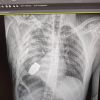

Операція під наглядом саперів: з тіла бійця ЗСУ дістали гранату ВОГ, що не розірвалася 🤯

☝️ Операція проводилася одним з найдосвідченіших хірургів ЗСУ – Андрієм Вербою без електрокоагуляції, оскільки граната могла детонувати у будь-який момент.

Військовослужбовця було відправлено на подальшу реабілітацію та відновлення.